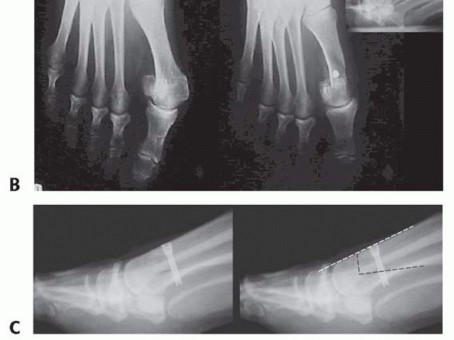

Hallux valgus must be assessed with a minimum of anteroposterior (AP) and lateral weight-bearing radiographs of the foot.

The HVA is determined by the intersection of the diaphyseal axes of the first metatarsal and the proximal phalanx. Arbitrarily, a normal HVA does not exceed 15 degrees (FIG 1A).

The IMA is the angle between the diaphyseal axes of the first and second metatarsals. Arbitrarily, a normal IMA does not exceed 9 degrees (FIG 1B).

The sesamoid position is determined by its relationship with the first metatarsal diaphyseal axis. Typically, the sesamoids remain in their anatomic position; with progressive hallux valgus deformity, the first metatarsal head progressively subluxates medially in relation to the sesamoids.

Normal (grade 0) sesamoid position: The tibial and fibular sesamoids are equidistant from the bisecting line of the first metatarsal.

Sesamoid position grades 1 to 3: Grades 1 through 3 signify an increasingly greater lateral position of the tibial sesamoid relative to the bisecting line of the tibial shaft axis, with grade 3 indicating that the tibial sesamoid is positioned completely lateral to the reference line (FIGS 1C and 2).

FIG 1 • AP radiograph of a patient with hallux valgus. Left, HVA (up to 15 degrees). Second from left, first IMA (up to 9 degrees). Second from right, sesamoid position. In this patient, the tibial sesamoid is divided into two halves by the diaphyseal axis of the first metatarsal, which means the beginning of a grade 2

sesamoid subluxation (normal is grade 0). Right, relative length of the first and second metatarsals; normal is up to 5 mm.

FIG 2 • Evaluation of hallucal sesamoid position. Grade 0, no displacement of sesamoids relative to the middle diaphyseal axis of the first metatarsal (normal). Grade 1, overlap of less than 50% of the tibial (medial) sesamoid to the reference line. Grade 2, overlap of more than 50% of the tibial sesamoid to the reference line. Grade 3, tibial sesamoid completely displaced beyond the reference line.

The interphalangeal angle (IPA) is measured between the axis of both the proximal and distal phalanx of the great toe; arbitrarily, its normal value is up to 10 degrees.

The DMAA is obtained by the intersection of the line that connects the articular edges of the head and the line bisecting the first metatarsal shaft. The DMAA normal value is up to 8 degrees (FIG 3).13,18 Inter- and intraobserver reliability for measuring the DMAA is poor.

The proximal phalanx articular angle is measured between the tangent to the proximal articular surface of the proximal phalanx of the great toe and the line bisecting the diaphyseal axis of the same phalanx. It is considered normal up to 10 degrees.

Relative length of the first and second rays is measured pre- and postoperatively. Most osteotomies lead to shortening of the first metatarsal. In our experience, greater than 5 mm of first metatarsal shortening of the first metatarsal frequently results in transfer metatarsalgia (FIG 1D).

The HVA, DMAA, and IMA are significantly higher in males, indicating that hallux valgus presents as a more severe deformity among males.14,15

FIG 3 • A. AP radiograph from a patient with juvenile hallux valgus in which the absolute congruence of the MTP joint can be noted. The misalignment of the distal articular surface of the metatarsal determines the hallux valgus deformity. B. Both edges of the metatarsal head articular surface are marked. The DMAA is measured between the line that connects the articular edges and the perpendicular to the diaphyseal axis of the first metatarsal. The normal value is up to 8 degrees.